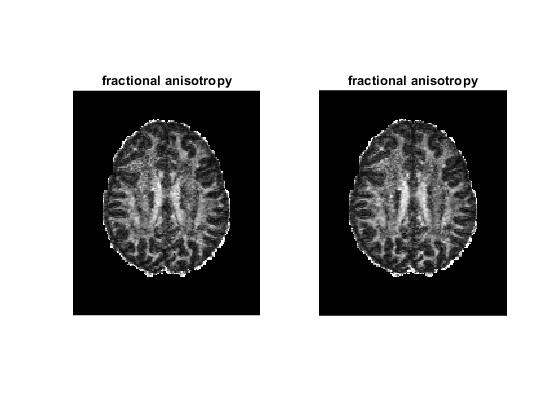

figure;

for ii = 1 : 2

tensor = tensor_all{ii};

subplot(1, 2, ii)

dtimetrics = decompose_tensor(tensor, mask);

fa = dtimetrics.fa;

imshow(rot90(fa(:, :, 35)), [0, 1])

title('fractional anisotropy');

end